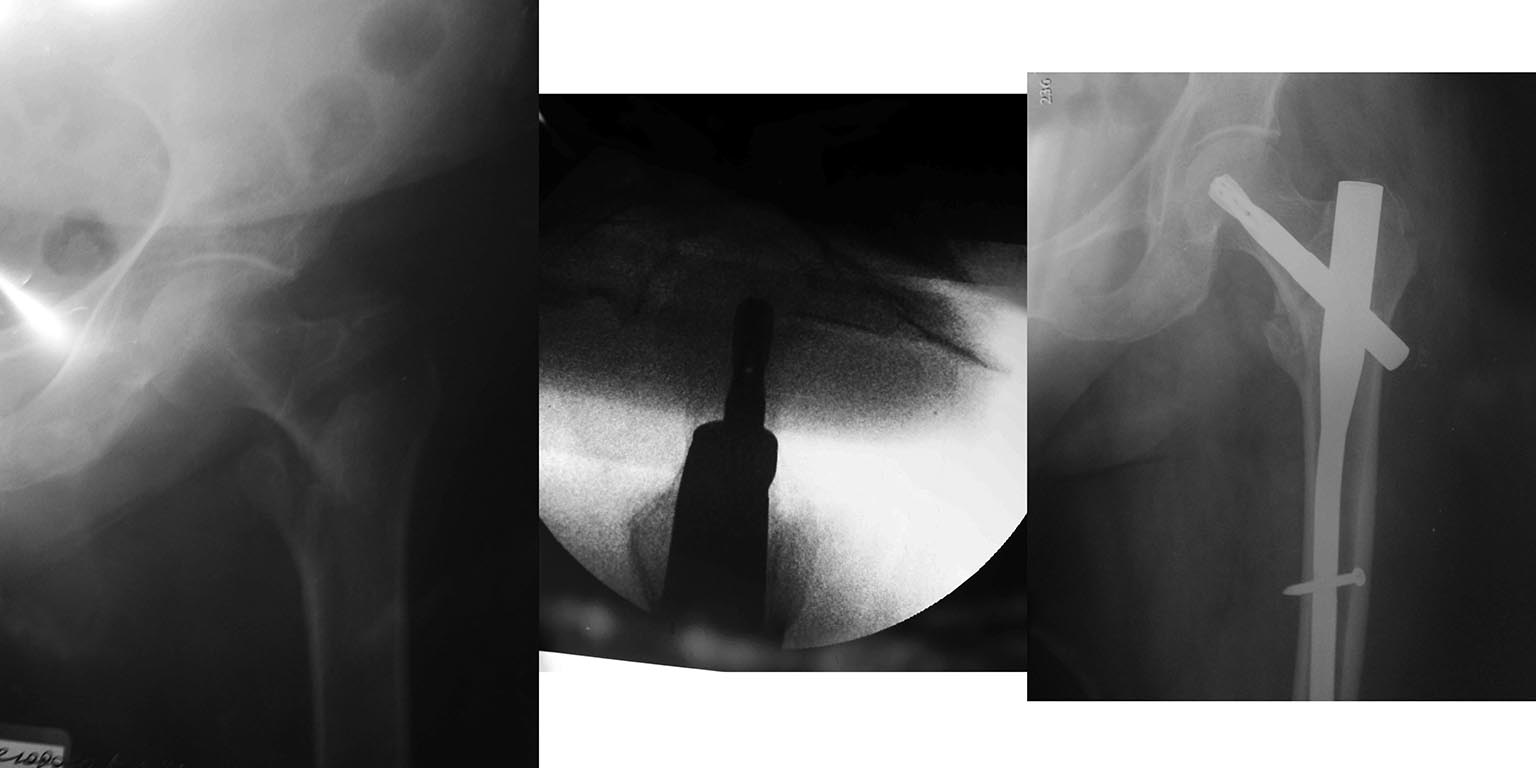

Добрый день, уважаемые коллеги! Перелом шейки левой бедренной кости у

пациентки 1940 года рождения.Женщина без серьёзной сопутствующей

патологии. Операция БИОС перелома шейки бедра через 5 суток после травмы

стержнем PFNa synthes.

Подскажите, пожалуйста, какой выбрать режим нагрузки на левую нижнюю

конечность. Наш план : один месяц с костылями без нагрузки на левую

нижнюю конечность, затем, после Rg контроля, давать дозированную

нагрузку с ходунками. Заранее благодарен!